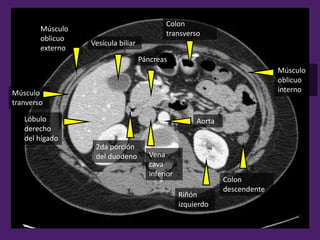

Músculo

oblicuo

interno

externo

tranverso

Vesícula biliar

Páncreas

Colon

transverso

Aorta

2da porción

del duodeno

Riñón

izquierdo

Lóbulo

derecho

del hígado

Vena

cava

inferior

3ra porción

Vena mesentérica

superior

descendente

Asas

yeyunoileales